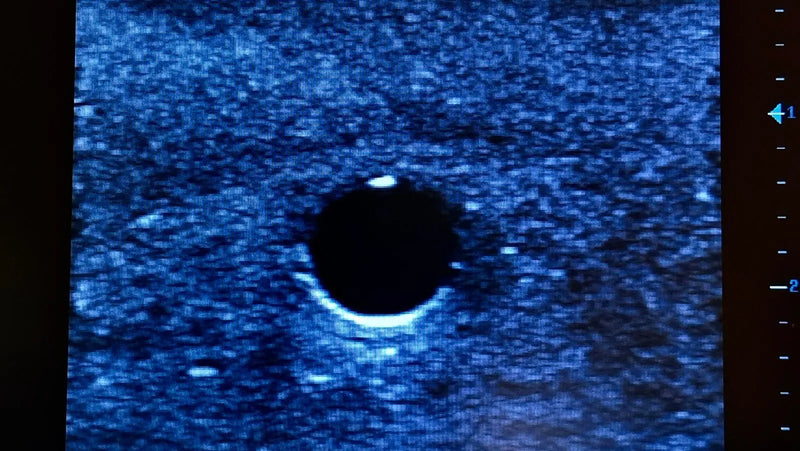

Thiết bị huấn luyện đơn giản, mạnh mẽ cho phép luyện tập lặp đi lặp lại kỹ thuật xâm nhập dưới hướng dẫn siêu âm một cách thực tế, giúp nâng cao thành thạo máy siêu âm, khéo léo sử dụng đầu dò và nhận biết cấu trúc giải phẫu. Tất cả chỉ với việc chuẩn bị và bảo trì tối thiểu.

Máy huấn luyện siêu âm BIOTME® mô phỏng mô người thật cả về cảm giác và đặc tính phản hồi sóng siêu âm. Vết kim sẽ biến mất sau vài ngày luyện tập, tăng cường tính chân thực và tiết kiệm chi phí.

Thiết bị huấn luyện đơn giản, mạnh mẽ cho phép luyện tập lặp đi lặp lại kỹ thuật xâm nhập dưới hướng dẫn siêu âm một cách thực tế, giúp nâng cao thành thạo máy siêu âm, khéo léo sử dụng đầu dò và nhận biết cấu trúc giải phẫu. Tất cả chỉ với việc chuẩn bị và bảo trì tối thiểu.

Máy huấn luyện siêu âm BIOTME® mô phỏng mô người thật cả về cảm giác và đặc tính phản hồi sóng siêu âm. Vết kim sẽ biến mất sau vài ngày luyện tập, tăng cường tính chân thực và tiết kiệm chi phí.

Thiết bị huấn luyện đơn giản, mạnh mẽ cho phép luyện tập lặp đi lặp lại kỹ thuật xâm nhập dưới hướng dẫn siêu âm một cách thực tế, giúp nâng cao thành thạo máy siêu âm, khéo léo sử dụng đầu dò và nhận biết cấu trúc giải phẫu. Tất cả chỉ với việc chuẩn bị và bảo trì tối thiểu.

Máy huấn luyện siêu âm BIOTME® mô phỏng mô người thật cả về cảm giác và đặc tính phản hồi sóng siêu âm. Vết kim sẽ biến mất sau vài ngày luyện tập, tăng cường tính chân thực và tiết kiệm chi phí.

Thiết bị huấn luyện đơn giản, mạnh mẽ cho phép luyện tập lặp đi lặp lại kỹ thuật xâm nhập dưới hướng dẫn siêu âm một cách thực tế, giúp nâng cao thành thạo máy siêu âm, khéo léo sử dụng đầu dò và nhận biết cấu trúc giải phẫu. Tất cả chỉ với việc chuẩn bị và bảo trì tối thiểu.

Máy huấn luyện siêu âm BIOTME® mô phỏng mô người thật cả về cảm giác và đặc tính phản hồi sóng siêu âm. Vết kim sẽ biến mất sau vài ngày luyện tập, tăng cường tính chân thực và tiết kiệm chi phí.